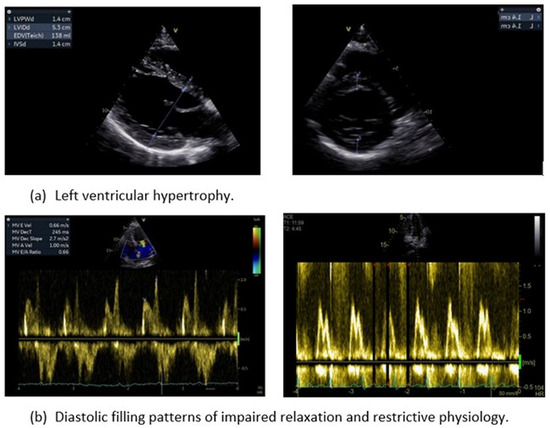

3.4. Diastolic Dysfunction